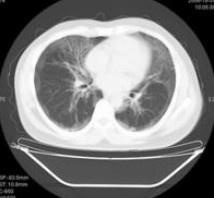

肺泡蛋白質(zhì)沉積癥癥狀

• 肺泡蛋白質(zhì)沉積癥

628健康網(wǎng)為您分享有關(guān)肺泡蛋白質(zhì)沉積癥的癥狀,肺泡蛋白質(zhì)沉積癥的治療方法,肺泡蛋白質(zhì)沉積癥的預(yù)防知識(shí),肺泡蛋白質(zhì)沉積...